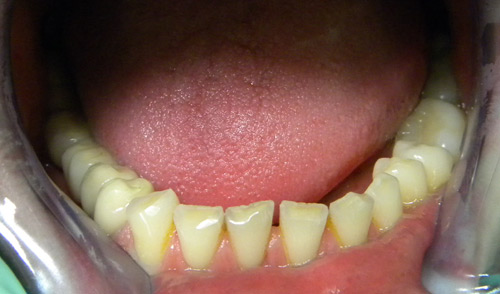

• Metalokeramičke krunice (prije)

• Bezmetalna keramika (prije)